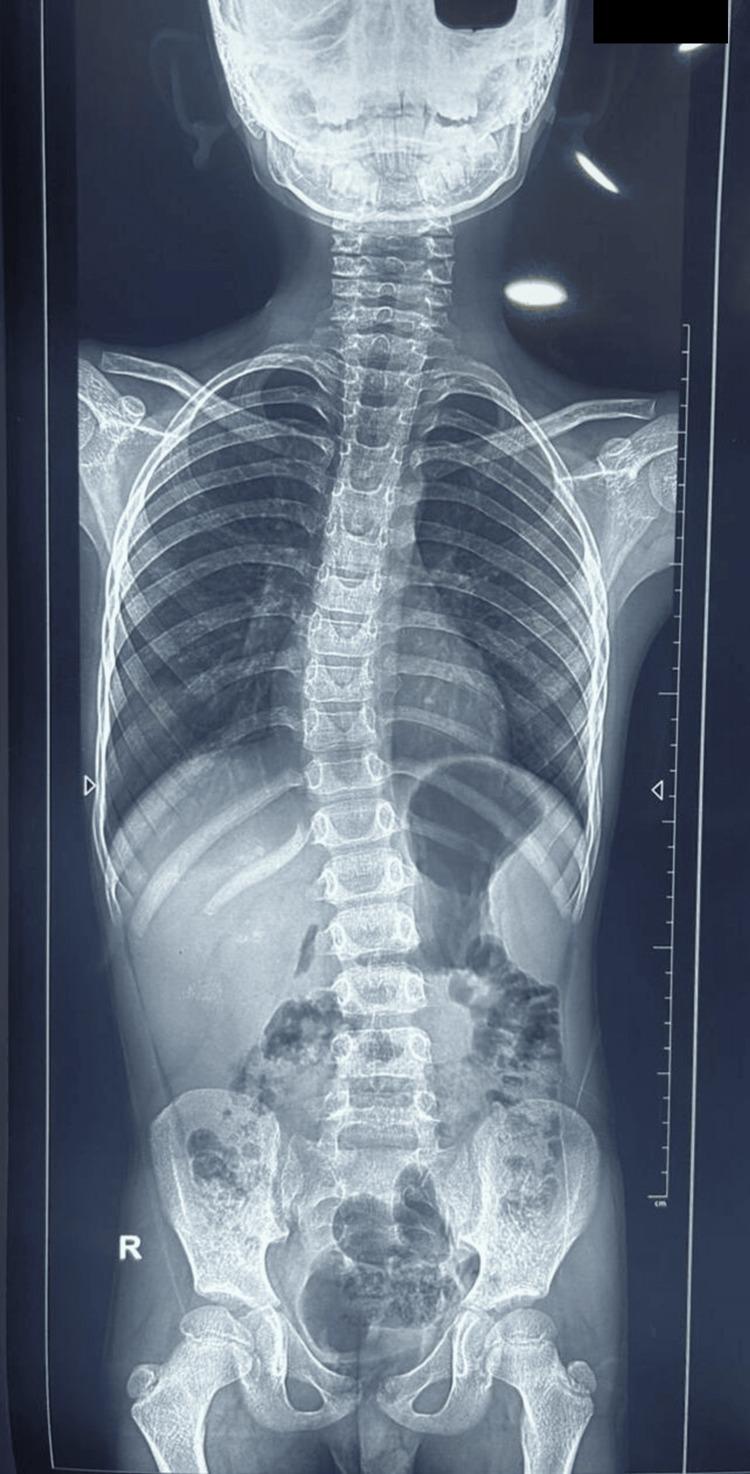

Horizontal gaze palsy with progressive scoliosis (HGPPS) is a rare autosomal recessive disease associated with mutation in the Roundabout-3 (ROBO3) gene (chromosome 11q23-25). Here, we present case report of a 7-year old male child born out of consanguineous marriage with history of similar condition in paternal uncle. The child had typical findings of HGPPS, i.e., horizontal gaze palsy, scoliosis, and characteristic findings on MRI associated with homozygous c.575G>A (p.Gly192Asp) mutation in ROBO3 gene. Additionally, mutation in G6PD gene was also observed in this patient, hypothesizing possible association between the two.

伴有进行性脊柱侧凸的水平凝视麻痹(HGPPS)是一种罕见的常染色体隐性疾病,与轴突导向分子-3(ROBO3)基因(位于11号染色体q23 - 25区域)突变相关。在此,我们报告一例7岁男性患儿,其父母为近亲结婚,患儿的叔祖父有类似病史。该患儿具有HGPPS的典型表现,即水平凝视麻痹、脊柱侧凸,且MRI有特征性表现,同时ROBO3基因存在纯合的c.575G>A(p.Gly192Asp)突变。此外,该患者还检测到葡萄糖-6-磷酸脱氢酶(G6PD)基因的突变,推测二者可能存在关联。